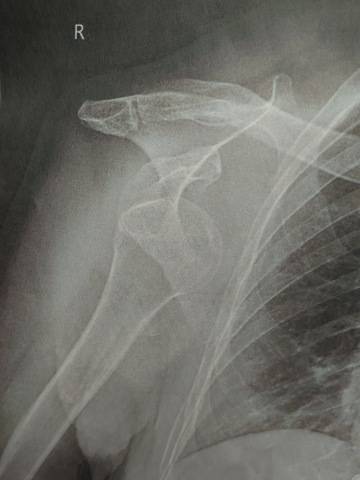

こちらの画像は

『転倒して右肩を脱臼した母の レントゲン写真 』 !!!

数日前、3センチほどの段差に少し大きめのスリッパを履いていた為につまづいてしまい転倒したらしい。

帰宅すると、肩から三角巾で右腕を吊るしている母にビックリ‼️

幸い脱臼だけで済んだけど、肩が外れた画像を見たことがなかったので皆さんにもお裾分けします!

午前中に私がいつもお世話になっている整体の先生に画像を見てもらうと

『前方脱臼ですね』と一言。

1番多いタイプなんだとか。

母いわく

「転んだ瞬間『メギっ!』って変な音がした!」